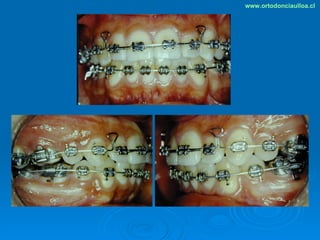

Este documento presenta dos casos clínicos de pacientes que recibieron tratamiento de ortodoncia. El primer caso fue de una paciente femenina de 14 años con apiñamiento dental y mordida cruzada que fue tratada mediante extracción de premolares y alineamiento dental. El segundo caso fue de un paciente masculino de 14 años con clase II esqueletal y desarmonía dentomaxilar que fue tratado con extracción de premolares y corrección de mordida. Ambos casos mostraron mejoría después de 3 años de tratamiento.